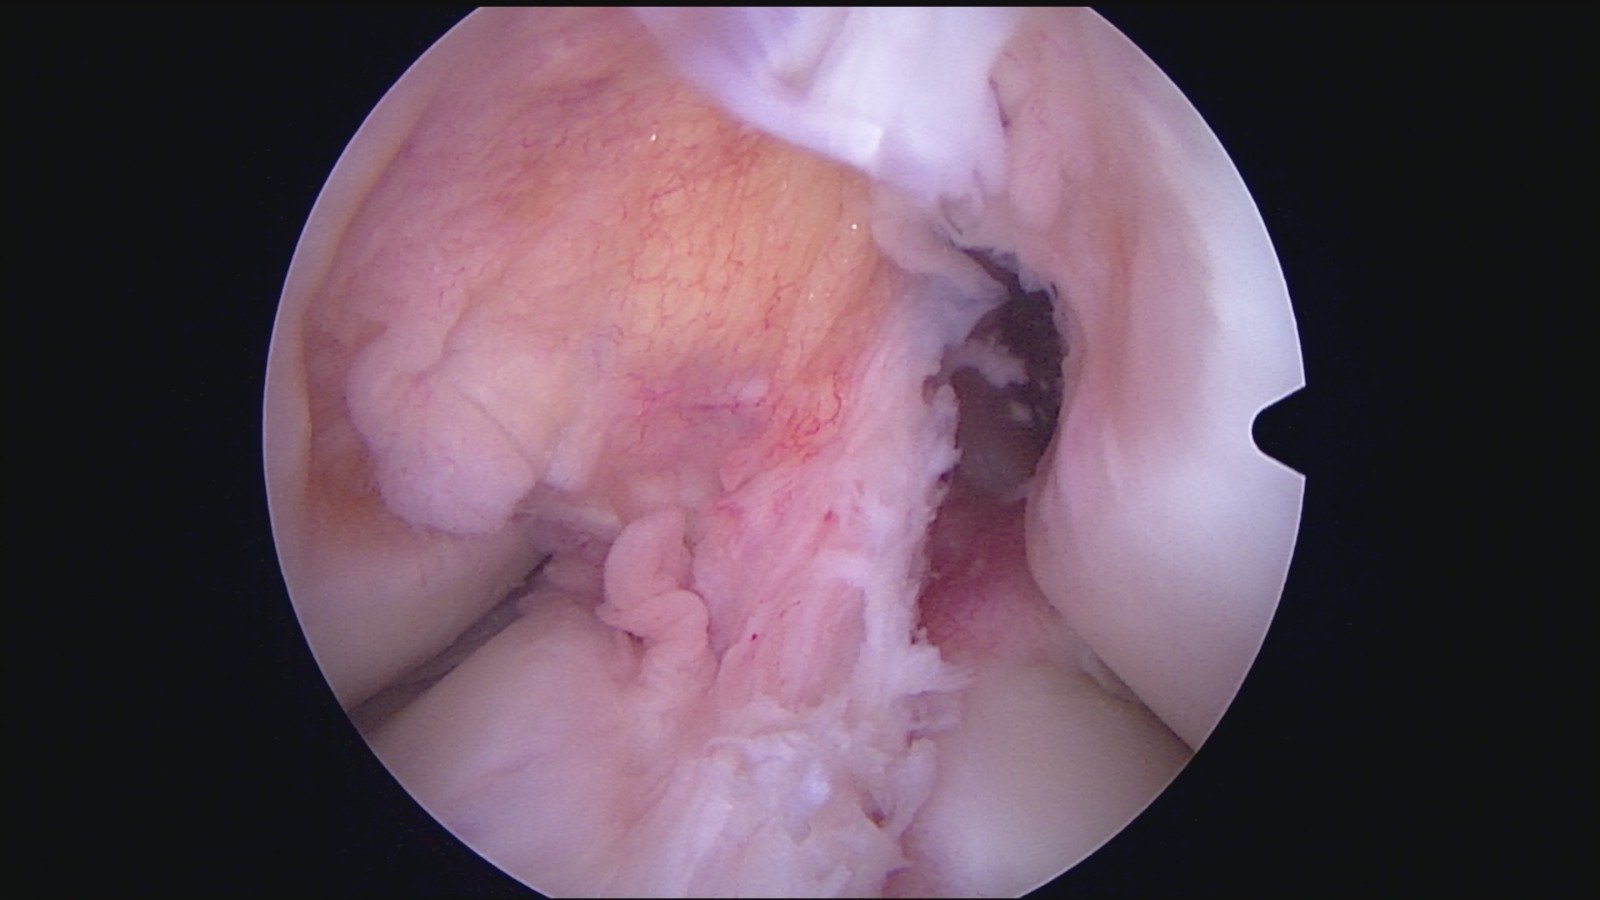

GalleryShoulder rotator cuff repair Meniscus root repair Meniscus repair Bankart repair for recurrent shoulder dislocation ACL reconstruction Machines Instruments